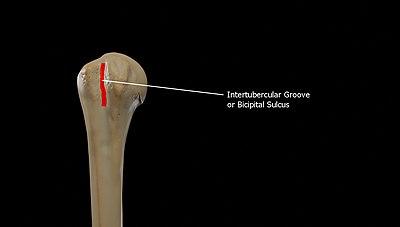

Bicipital groove

The tubercles are separated from each other by a deep groove, the bicipital groove (intertubercular groove; bicipital sulcus), which lodges the long tendon of the biceps brachii muscle and transmits a branch of the anterior humeral circumflex artery to the shoulder-joint. It runs obliquely downward, and ends near the junction of the upper with the middle third of the bone. In the fresh state its upper part is covered with a thin layer of cartilage, lined by a prolongation of the synovial membrane of the shoulder-joint; its lower portion gives insertion to the tendon of the latissimus dorsi muscle. It is deep and narrow above, and becomes shallow and a little broader as it descends. Its lips are called, respectively, the crests of the greater and lesser tubercles (bicipital ridges), and form the upper parts of the anterior and medial borders of the body of the bone.[2]